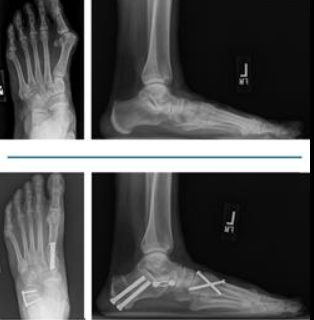

수술 치료: 매우 심하거나 보존적 치료에 반응하지 않을 때 시행한다.